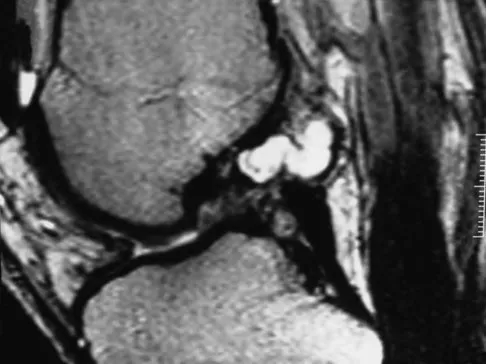

Figure 30 shows the MRI scan of a 68-year-old woman who has left hip pain. What is the most appropriate treatment?

The patient has a large zone of osteonecrosis of the left femoral head. The wedge-shaped zone of decreased signal intensity on the T1 image in the subchondral region of the femoral head is typical. Based on these findings, total hip arthroplasty is the most appropriate treatment. Open reduction and internal fixation will not help this condition. Incisional biopsy is indicated only if the MRI scan shows a probable neoplasm. Resection of the proximal femur is indicated only for aggressive malignancy. Arthrodesis may be considered in a younger patient but not in a 68-year-old individual. Other treatments, not listed, such as core decompression, vascularized fibular transplant, and osteotomy may be options in selected patients. Urbaniak JR, Jones JP Jr (eds): Osteonecrosis: Etiology, Diagnosis, and Treatment. Rosemont, IL, American Academy of Orthopaedic Surgeons, 1997, pp 213-223.